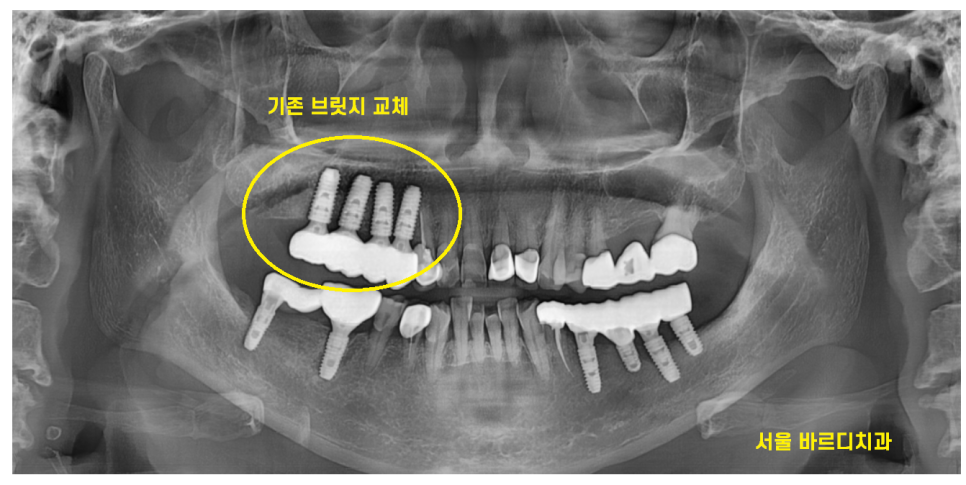

해당 환자분은 한쪽 치료가 끝나갈즈음

반대편 보철이 빠져버렸습니다.

문제의 치아 입니다.

묶어있는 형태였는데요.

23.10.10

아직 반대편 치료가 다 끝나지 않았는데

기존 보철이 빠져버렸네요ㅠㅠ

기존 금니 보철이 빠진 후

임플란트로 교체 해드렸습니다.